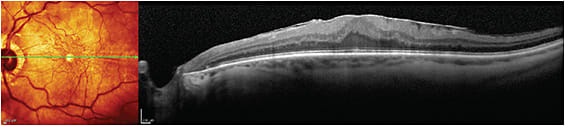

Right eye with lamellar macular hole.

IMAGE COURTESY STEVEN G. SAFRAN, MD